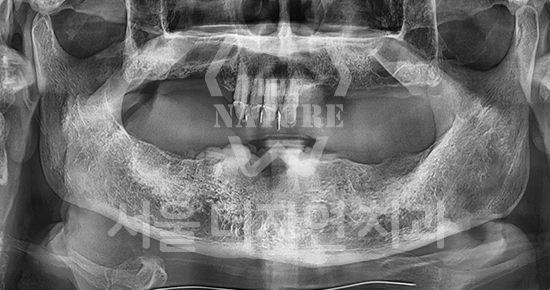

#Full Mouth Implants

-

BEFORE: 2022.12.15

AFTER: 2023.02.23

#Sinus Lift

BEFORE: 2021.02.01

AFTER: 2021.05.13

#Maxillary Bone Grafting

BEFORE: 2021.11.02

AFTER: 2022.01.19

Treatment outcomes may vary by patient,

and side effects may occur.

These images were taken under the same conditions,

and were published with the patient's consent.